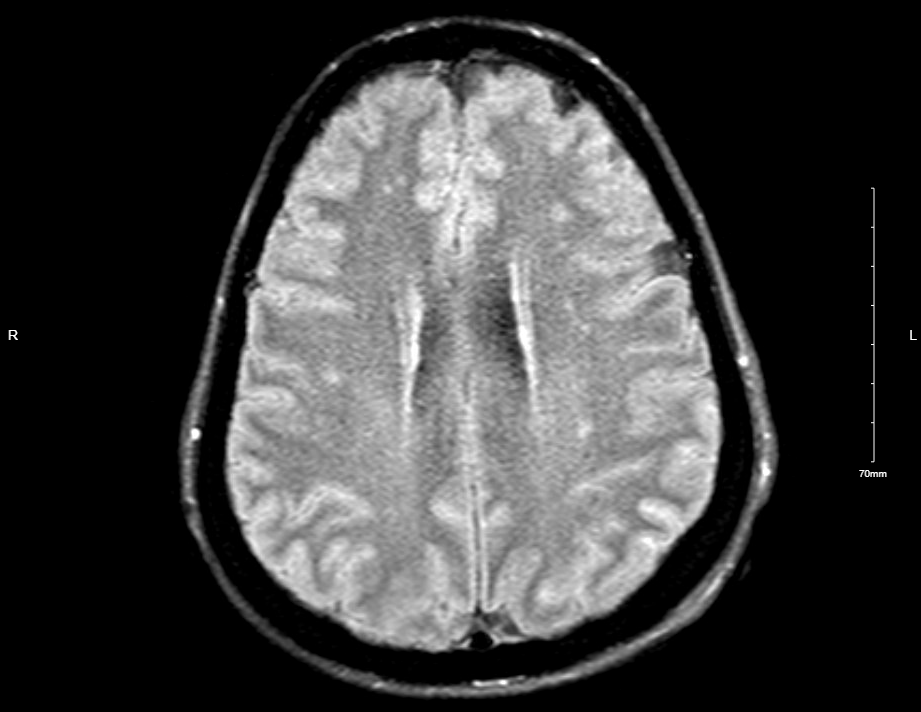

Case Presentation: A 44-year-old woman with past medical history of anxiety, depression, and seizure disorder presented with seizure-like activity consisting of asynchronous bilateral upper and lower extremity shaking, throughout which patient was alert and responsive. Patient had a 5-year history of these episodes, with a recent increase in frequency exacerbated by stress. Prior extensive workup included multiple video electroencephalograms with no epileptiform activity. Patient was prescribed antiepileptics, antidepressants, and anxiolytics to which she was adherent. Patient had no personal or family history of thyroid disease, diabetes, or autoimmune conditions.Later in the hospital course, the patient became obtunded, tachycardic, tachypneic, and hypotensive requiring pressor support and intubation. During episodes, patient had marked anisocoria and increased tone and rigidity in truncal and proximal muscle groups, with flaccid distal muscles and neck muscles, which resolved between episodes. Chest x-ray showed pulmonary vascular congestion and transthoracic echocardiogram showed reduced ejection fraction consistent with stress cardiomyopathy. Labs were remarkable for metabolic acidosis and elevated CK and lactate levels. Initial cerebrospinal fluid analysis was unremarkable. Anti-GAD antibodies were positive (>250 IU/mL) and anti-NMDA antibodies were negative. Patient developed acute DVT requiring anticoagulation, which was then held in the setting of a retroperitoneal hematoma. Patient was treated with plasmapheresis alternating with stress-dose steroids and patient’s neurological and cardiovascular function fully recovered. Patient was discharged in stable condition to an acute rehabilitation facility.